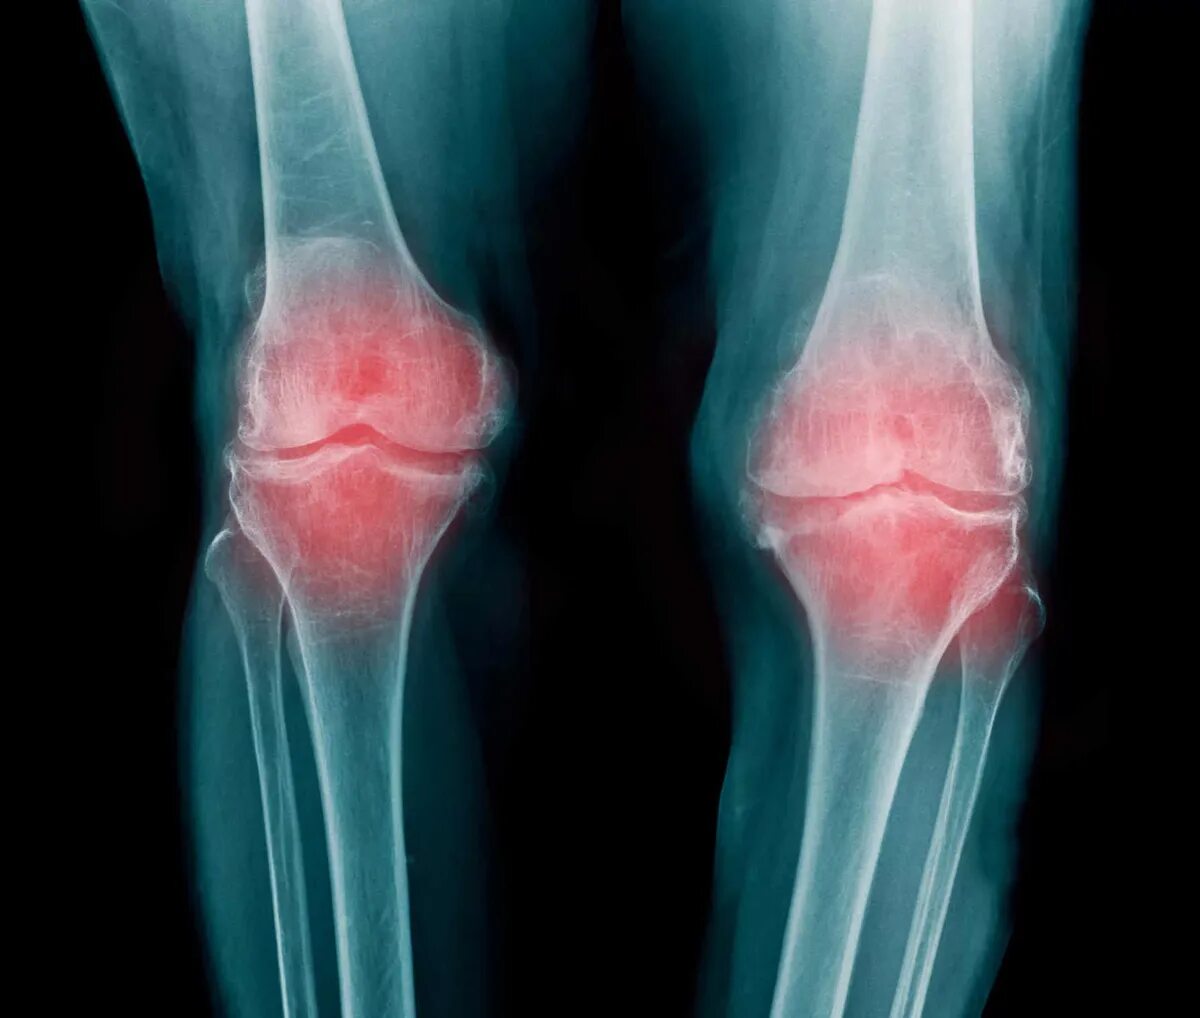

Остеоартрит 2025